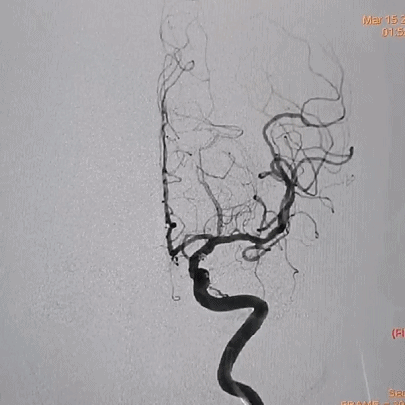

术前影像

栓塞过程

首先将Jasper®弹簧圈填入动脉瘤腔内成篮,然后向动脉瘤远端小阜填入Jasper®SS弹簧圈一枚,动脉瘤顶端小阜栓塞效果良好,并可以致密填塞小阜部分。然后填入Jasper®弹簧圈、Jasper®SS弹簧圈各一枚,造影显示胚胎型大脑后动脉保留完好,动脉瘤致密栓塞,瘤颈处无残余。

在微导丝引导下超选入海绵窦段动脉瘤瘤腔内,根据动脉瘤大小选择Jasper®SS弹簧圈一枚,栓塞过程中Jasper®SS弹簧圈经调整后可稳定填入小动脉瘤腔内。

术后即刻影像

对于有小阜的破裂动脉瘤,小阜内可使用较为柔软的弹簧圈进行栓塞,避免成篮弹簧圈压缩,减少动脉瘤再破裂风险。微小动脉瘤栓塞较为困难,微导管塑形及选择合适弹簧圈是关键。Jasper®SS弹簧圈系列圈体柔软,对于微小动脉瘤的填塞更加安全,且栓塞更加致密,提高患者疗效。